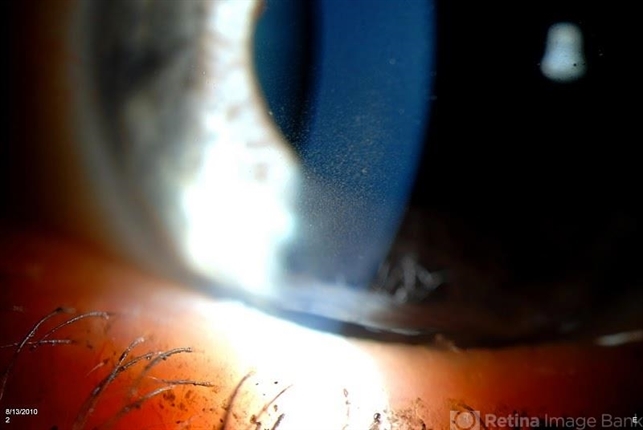

- Krukenbergs Spindle

- Krukenberg's spindle

Photo slit lamp biomicroscope

TOPCON D-90 SL NIKON CAMERA - Description

- Slit lamp shows pigment on the lower quadrant of the endothelium due to pigment dispersion glaucoma.